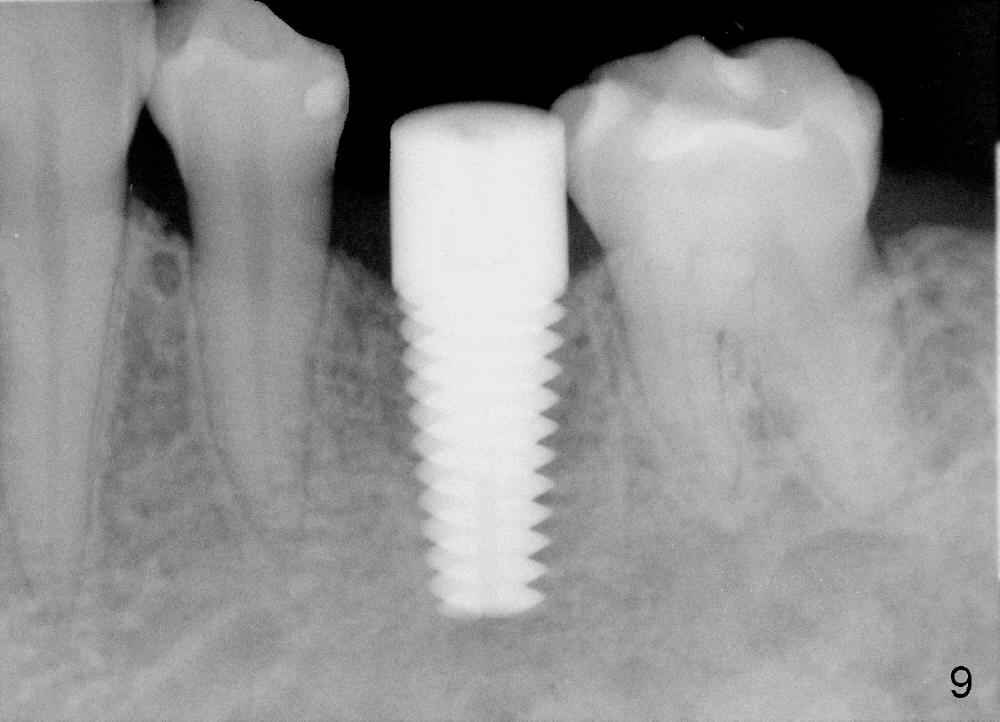

Six months postop, bone density around the implant increases (Fig.9). There is slight gingival recession buccal to the implant (Fig.10 arrow). A short abutment is placed and prepared short (Fig.11 A); the margin is prepared as low as possible in the implant (I).

Eleven months post bonding (17 months postop), there is cortical bone formation at the mesial and distal crests (Fig.14). It remains the same 1 year 10 months post bonding (Fig.15). There is no bone loss 3 years 5 months post cementation (Fig.16). In fact the crestal cortical bone thickens.